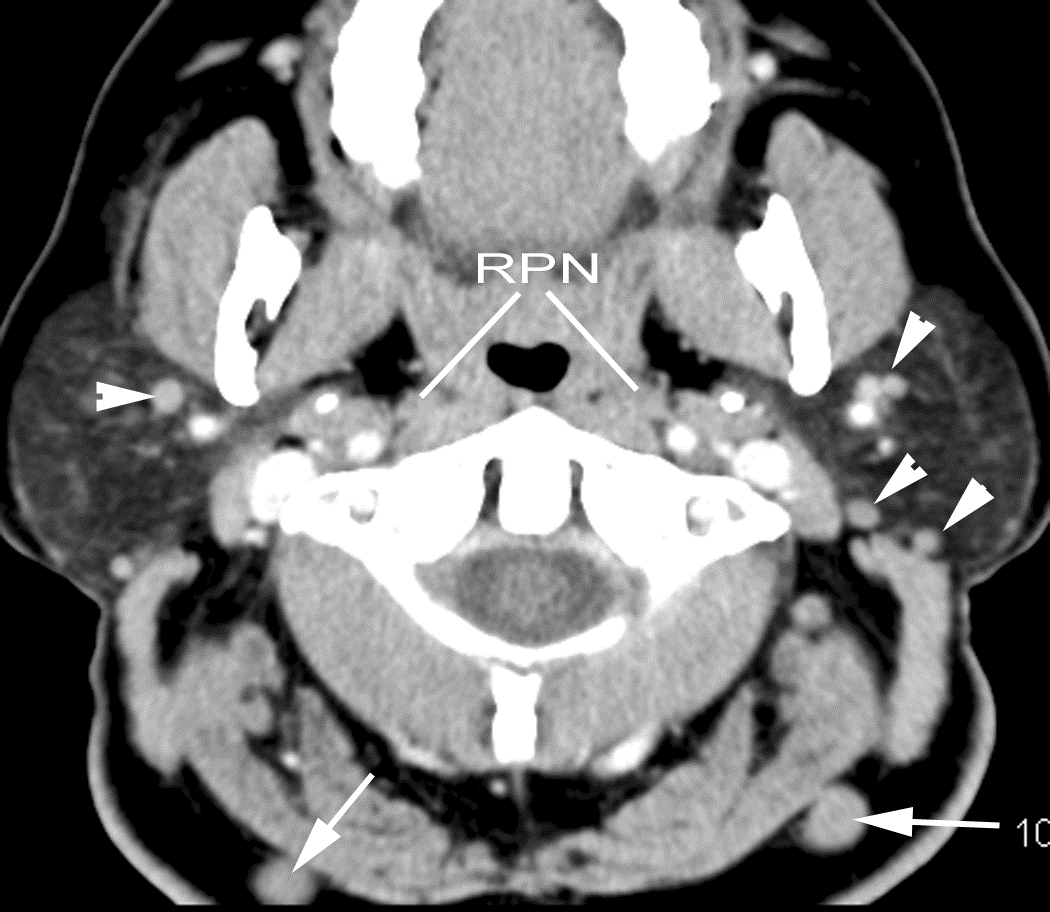

The other cervical (Levels 2-6), supraclavicular and/or retropharyngeal lymph nodes are abnormal by imaging criteria. [Yes/No]